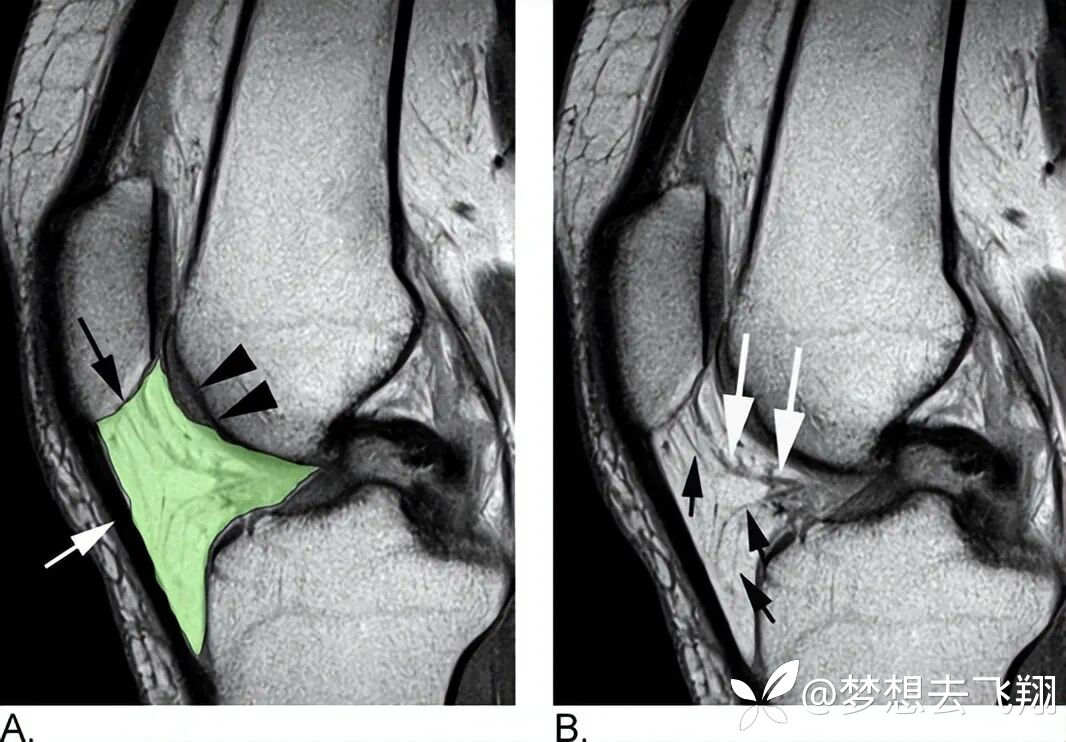

先看MRI所示的正常Hoffa脂肪垫(图6)。

图6:Hoffa脂肪垫的MRI解剖图例,参考6

对图6的解释:A. 矢状面T1加权自旋回波MRI。髌下脂肪垫(IPFP)是一个位于关节囊内但滑膜外的结构(绿色透明部分),其前侧受髌腱(白色箭头)限制,后侧受滑膜衬里的膝关节限制。其上侧附着于髌骨下表面(黑色箭头),并通过两个翼状滑膜皱襞向后延伸至髁间窝,这两个皱襞融合形成髌下皱襞。Hoffa脂肪垫的上后侧与股骨滑车软骨相邻(黑色箭头)。B. 无重叠的相同图像显示脂肪垫内可见低信号灶,代表髌下皱襞(白色箭头)和血管(小黑箭头)。